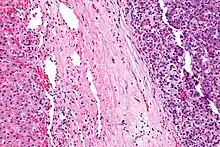

| Micrograph of a hepatoblastoma. H&E stain. | |

Hepatoblastoma is a malignant liver cancer occurring in infants and children and composed of tissue resembling fetal liver cells, mature liver cells, or bile duct cells. They usually present with an abdominal mass. The disease is most commonly diagnosed during a child's first three years of life.[1] Alpha-fetoprotein (AFP) levels are commonly elevated, but when AFP is not elevated at diagnosis the prognosis is poor.[2]